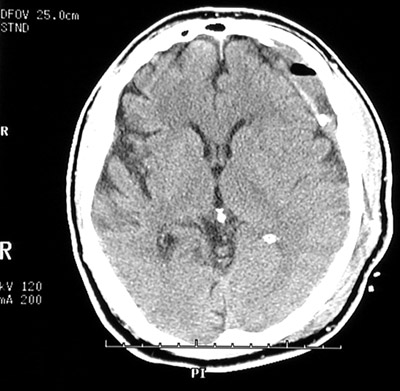

| A chronic subdural hematoma has been treated with evacuation of the organizing blood clot. The burr hole for the drain is drilled into the skull is seen on the right. In the view below of another case of chronic subdural hematoma following evacuation, the dark area near the hematoma on the left is air not yet resorbed following surgery. |